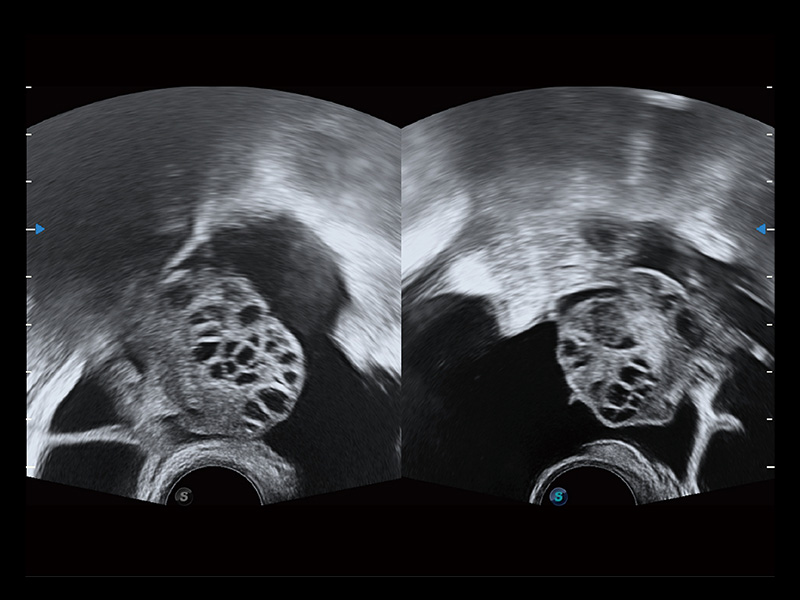

“生育问题”即关系民族复兴,也关系亿万家庭的幸福。随着婚育年龄推迟、社会压力增加等因素,越来越多人群也面临着“生不出、生不好”的问题。辅助生殖作为治疗不孕不育最有效的方法之一,也逐渐成为育儿新希望。而超声检查能为生殖需求人群的初诊评估提供宝贵的信息。 P20 Elite是哈哈体育官网匠心打造的一款生殖应用型彩超。她继承哈哈体育官网高端极光平台,突破性地将多款新型芯片及硬件模块进行整合,均衡了高端系统性能与小巧灵动机身。P20 Elite卓越的图像质量搭载专科探头,旨在为您提供全面的辅助生殖解决方案。

P20 Elite配备了丰富的生殖探头群和临床应用功能,在卵泡监测、穿刺取卵、胚胎移植、妊娠确认等领域,为生殖需求人群提供了新的临床机会,重新定义高端超声如何应用于生殖健康检查。